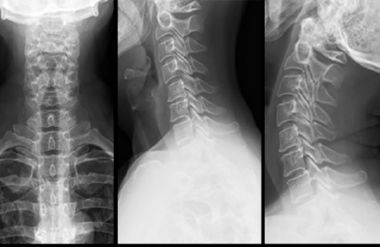

Если боль не проходит в течение 3–4 дней, необходимо сделать рентген грудного и шейного отделов позвоночника.

- Рентгенологическое исследование — при подозрении на артрит, спондилолистез или нарушения осанки.